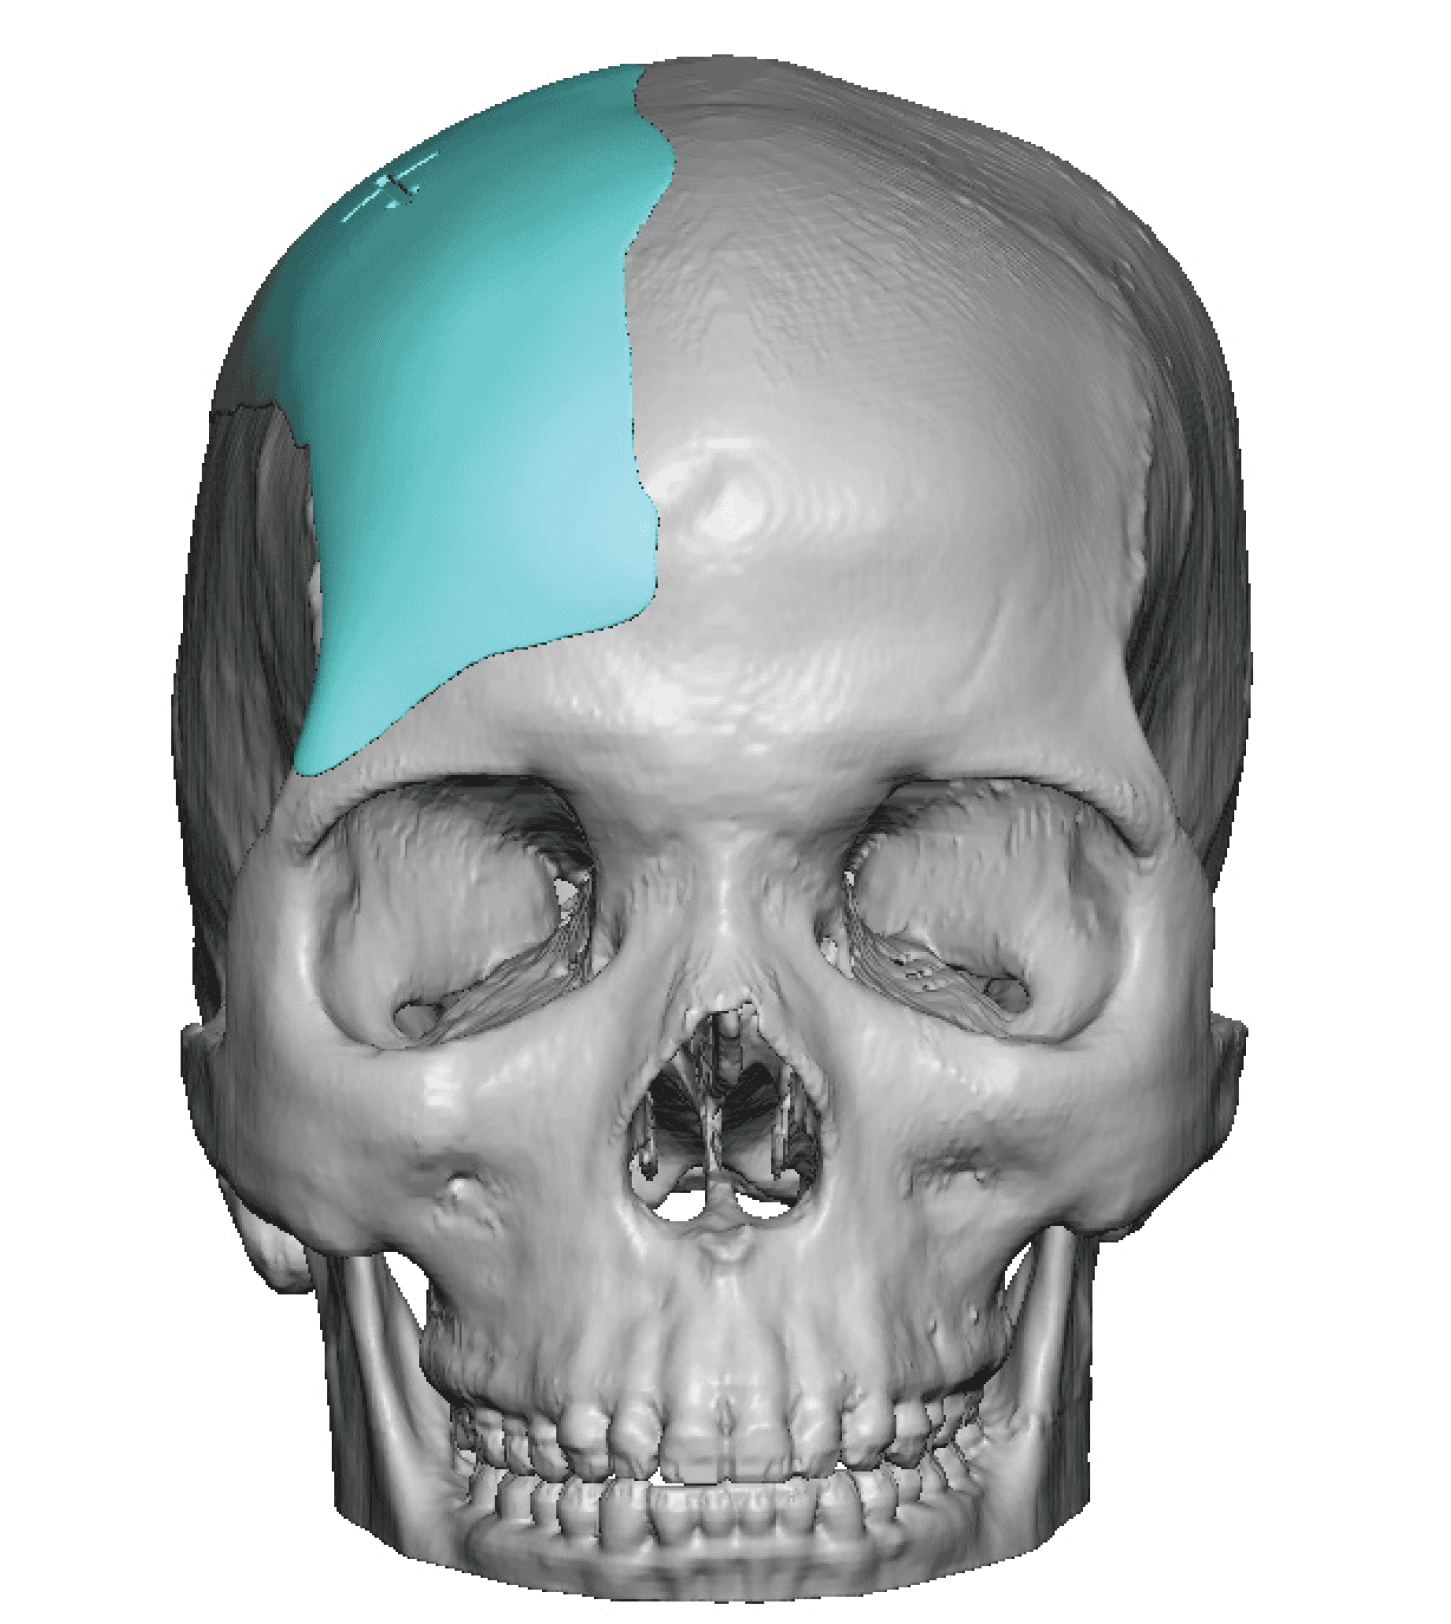

Reconstruction of loss of frontotemporal craniotomy bone flap from neurosurgery.

Reconstruction of full-thickness skull defect with computer-generated HTR-PMI cranial implant.

Reconstruction of loss of frontotemporal craniotomy bone flap from neurosurgery.

Reconstruction of full-thickness skull defect with computer-generated HTR-PMI cranial implant.